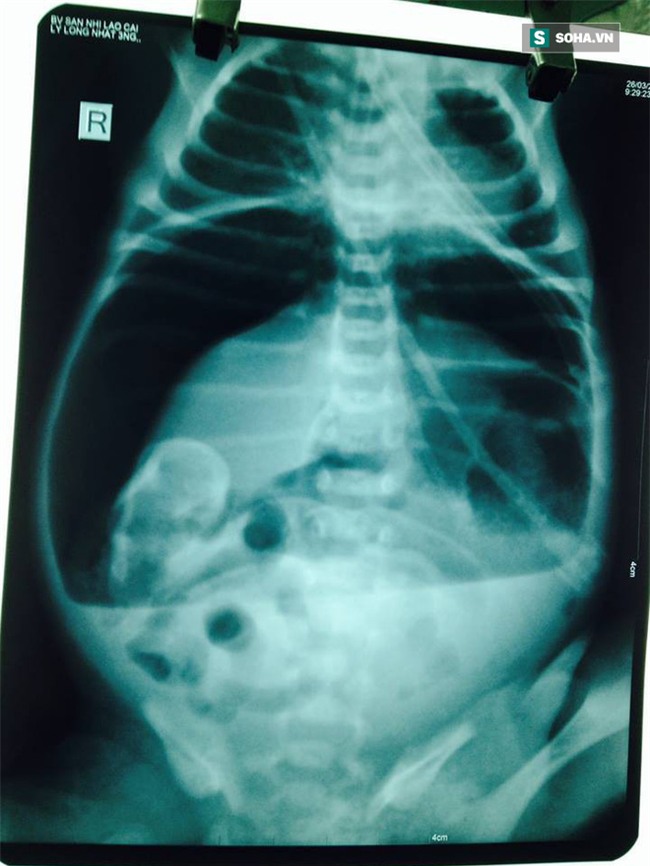

"Khi chúng tôi tiếp nhận trẻ ở trong tình trạng li bì, khó thở, tím, không sốt, bụng chướng căng, đặt sonde dạ dày có ít dịch màu xanh, bơm rửa trực tràng dịch nhày nâu lượng ít. Ngay sau đó trẻ được hồi sức tích cực bằng cách: trợ hô hấp, nuôi dưỡng hoàn toàn bằng đường tĩnh mạch, X-quang ổ bụng có hình ảnh mức nước - hơi và liềm hơi dưới cơ hoành.

Với tình trạng trẻ như vậy, chúng tôi đã hội chẩn cùng Ths.BS Đinh Ngọc Dũng - Trưởng khoa Ngoại tổng hợp - Bệnh viện Đa khoa tỉnh Lào Cai và chẩn đoán: Viêm phúc mạc do tắc ruột phân su biến chứng vỡ tạng rỗng", bà Nguyệt thông tin. Khi tiến hành phẫu thuật cấp cứu cho cháu bé, kíp phẫu thuật bất ngờ phát hiện dạ dày trẻ có cấu trúc bất thường.